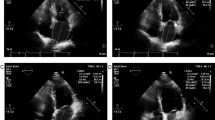

Echocardiography and STE

Data were measured in all patients by a transthoracic echocardiography system (iE33 machines equipped with X3; Philips Medical Systems, Eindhoven, The Netherlands) and included the LA anteroposterior diameter, LA ejection fraction (LAEF), LA maximum volume (LAVmax) and LA minimum volume (LAVmin).Left atrial strain (S) and strain rate (SR) were measured by two-dimensional speckle tracking technique. We manually traced three markers in the LAVmax view to obtain SR curves and calculated the average value in the two-chamber view10. Three consecutive cardiac cycles with a stable echocardiographic appearance were recorded. The new parameters of S and strain rate SR in echocardiography can fully reflect the functional status of left atrial. S and SR are closely related to the amplitude and rate of myocrdial deformation. The strain rate is divided into three parts: left ventricular systole (SRs) reflects left atrial storage function, left ventricular early diastolic (SRe) responds to left atrial channel function, and left atrial systole (SRa) reflects left atrial pump function, the bigger absolute values, the left atrial myocardial elasticity better. The abovementiond data were measured before and after the RFCA procedure (at 1, 2, 3, 4 weeks, and 2, 3, 6, and 9–12 months). All ultrasound data were measured twice by professional sonographers, with the average value used in the analysis.

Effects of RFCA on LA function

The LAEF, LA strain and SR at each follow-up timepoint in the three groups are shown in Table 3 and Fig. 3. There was no significant change in LAEF within 1 year in the paroxysmal AF group. The LAEF was significantly increased in the persistent AF and LSPAF 1 week after RFCA, and then increased sightly. In the paroxysmal AF group, there was no significant change in the LA strain in the two-chamber view within 1 year. In the persistent AF and LSPAF groups, the LA strain significantly increased after RFCA, especially within 1 week, and then increased slightly. The absolute values of the LA SR during left ventricular systole (SRs) and during LA systole (SRa) were significantly increased after RFCA compared with before the procedure in the persistent AF and LSPAF groups, the absolute values of the SR during early left ventricular diastole (SRe) did not significantly change compared with the pre-procedure value, but the absolute value had showed an upward increasing trend.